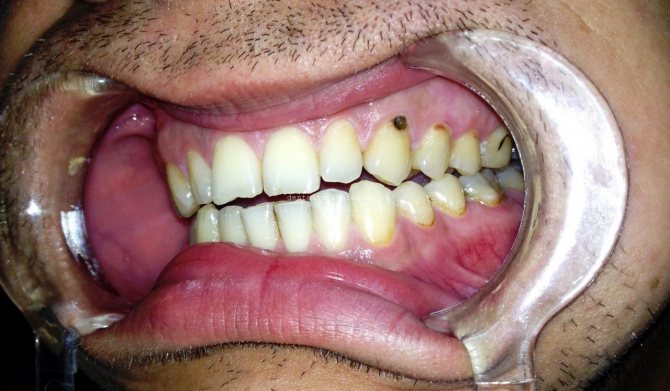

Фото: средняя и глубокая стадии